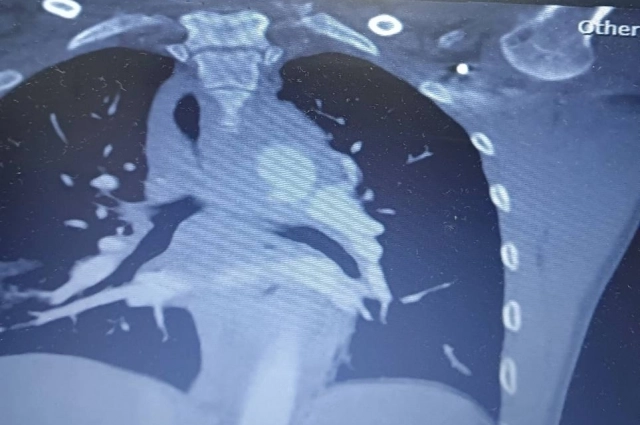

Аркадий и Ксения отправились на отдых в Таиланд 28 октября. Однако уже через несколько дней мужчина попал в страшную аварию. У него оказались сломаны ребра, травмирована нога, а также повреждена аорта. Как рассказала его супруга Ксения, у мужа произошёл пневмоторекс. Из-за удара у него ввозникла аневризма грудной аорты. Сейчас он лежит в больнице, причём страховая компания отказывается оплачивать лечение. Ситуацию усугубляет и то, что при транспортировке Аркадию может стать ещё хуже.

«Его нельзя транспортировать в Россию, так как аневризма может лопнуть в любой момент из-за перепада давления. Нам оказали первую помощь в госпитале Краби-таун, ему провели исследования на рентгене и КТ, выявили аневризму. Затем сказали, что мужа нужно перевозить в другой госпиталь, где есть сосудистый хирург. Так нас перевезли в город Хатъяй», — объяснила Ксения.